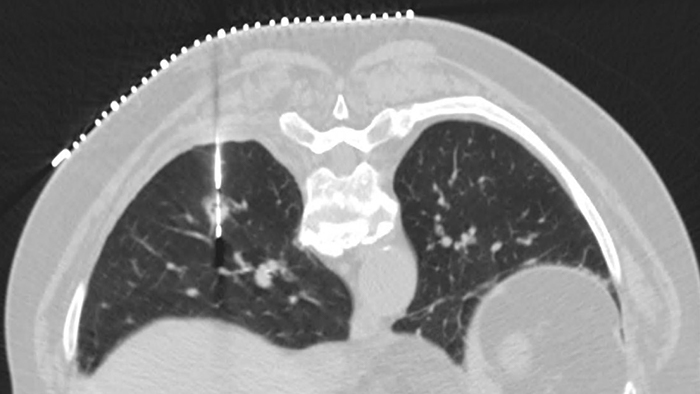

Сокращение времени проведения биопсии под контролем КТ на 16%2 Автоматический анализ траектории движения иглы, построение маршрута от точки входа до цели, расчёт глубины, угла, расстояния до цели и другие инструменты сокращают время проведения инвазивного исследования и повышают его точность.

ContinueАвтоматическое отслеживание иглы для сокращения времени выполнения интервенционных процедур

2 Chacko C. Precise Intervention Clinical Review Report for Loong. Philips Doc ID: D000874955. 2021.